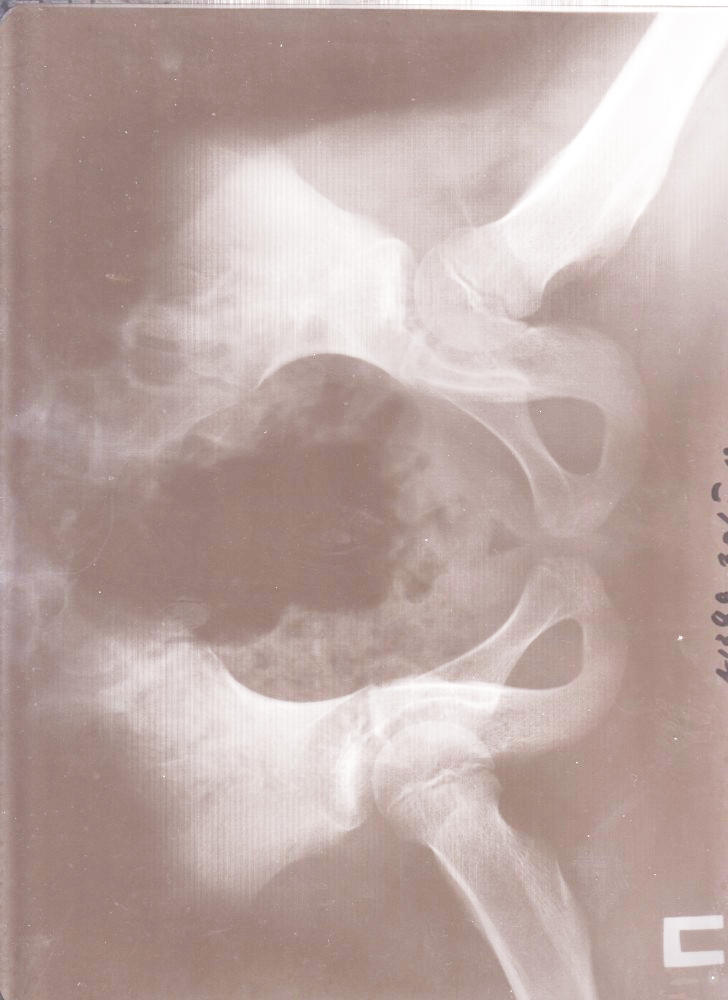

Пихнул, для интересу, снимки старые в обычный принтер. И ни че го. Черное поле и надпись фломастером по прозрачному краю. Так что не вариант.

С открытой крышкой такой же результат. А вот если открыть крышку и посветить фонарем что то проглядывает, но свет нужен яркий и равномерный.В принципе можно извернуться...

йа поэксперементировал и более менее результата добился подсвечивая вспышками двух телефонов.

Ну значицца вердикт- на бытовом сканере крышка открыта,свет как можно ярче, установки сканера- цветные, разрешение 300 уже хватает.

300 всё-же мало, думаю надо побольше, но файл получится тяжёлый. Ещё полосы получились вертикальные, но это ерунда, вся нужная информация видна. Яркость+ Контрасность+